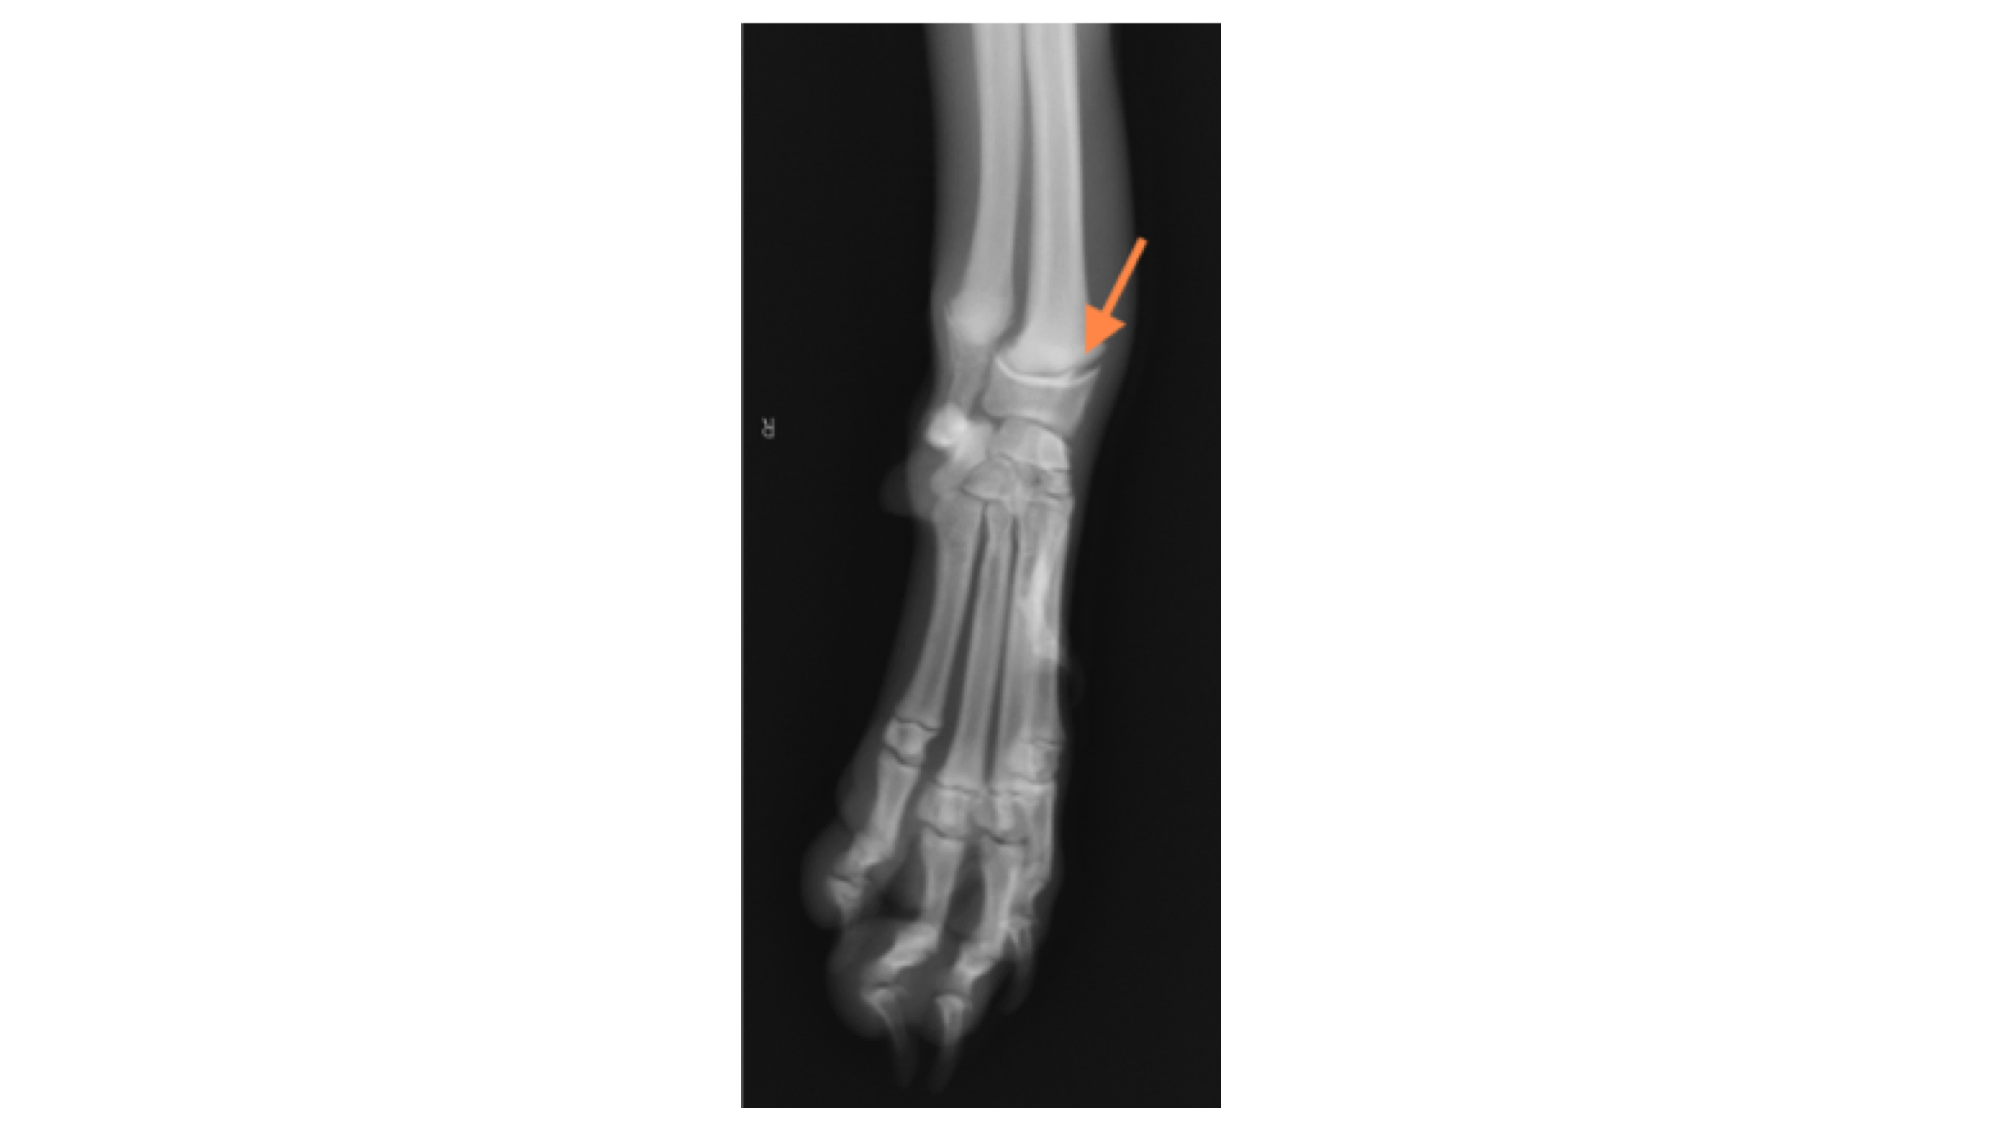

レントゲン検査を行ったところ、右手根骨のⅠ型成長板骨折が認められました。

→の部分が骨折部位になります。

この画像の曲線が、正常な成長板です。下の画像と比較してみると、わかりにくいですが骨折線が認められます。

成長板骨折は1方向だけのレントゲン画像では診断が難しいため、必ず2方向(横、正面)からの撮影を行います。